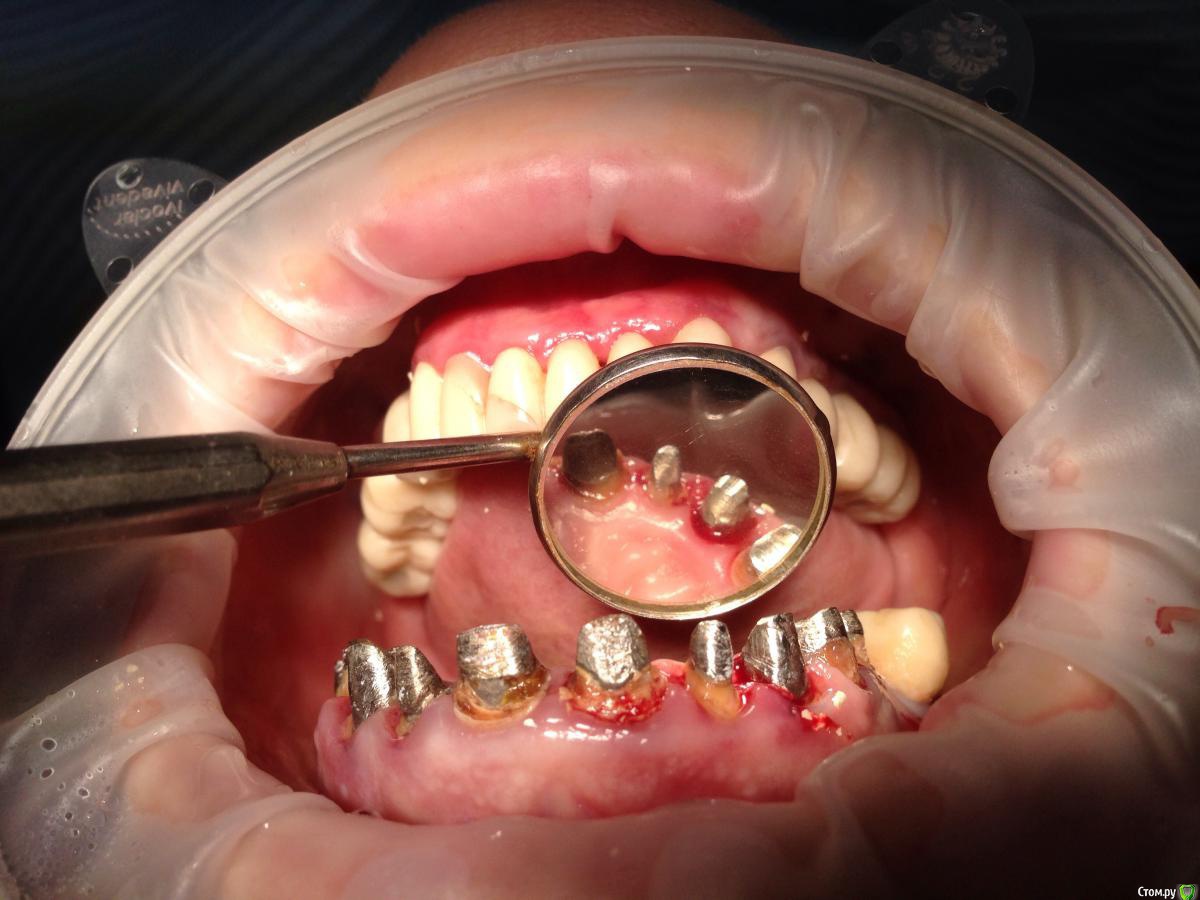

Bratok Опубликовано 17 июля, 2016 Поделиться Опубликовано 17 июля, 2016 Коллеги, всем привет! Вот такая пациентка в клинике был доктор у нас с 20 летним стажем, она уехала сейчас и не работает. Протезировала пациентку.. Были изготовлены временные коронки.. Судя по всему страдал герметизм и под ними все печально.. Десне и феррулу хана...Чтобы Вы тут посоветовали? Планировалось к нее мк... Сделать в 3 сегмента 3-3 и остальные блоком. Какой прогноз? Лет 5? Извиняюсь за качество rg.. Ссылка на комментарий

AndyAndy Опубликовано 17 июля, 2016 Поделиться Опубликовано 17 июля, 2016 Привет! М-да, печаль беда.... Мы же с вами понимаем что все это надо извлекать, убирать кариес и смотреть на то что останется. Возможно хир удлинение коронковой части. Пациентка как настроена вообще? вы наверняка объяснили ей чем она рискует. Но все- таки стремно так все оставлять. Там герметизм нарушен и между вкладками и стенками канала, 100%. Ссылка на комментарий

Bratok Опубликовано 17 июля, 2016 Автор Поделиться Опубликовано 17 июля, 2016 там нарушено все, что могло быть нарушено Ссылка на комментарий

korotkevich Опубликовано 17 августа, 2019 Поделиться Опубликовано 17 августа, 2019 (изменено) Коллеги, всем привет! Вот такая пациентка в клинике был доктор у нас с 20 летним стажем, она уехала сейчас и не работает. Протезировала пациентку.. Были изготовлены временные коронки.. Судя по всему страдал герметизм и под ними все печально..Десне и феррулу хана...Чтобы Вы тут посоветовали?Планировалось к нее мк...Сделать в 3 сегмента 3-3 и остальные блоком. Какой прогноз? Лет 5?Извиняюсь за качество rg..В идеале доставать вкладки, убирать кариозные ткани, делать билдапы и затем либо хирургическое удлинение, либо вертипреп, либо и то, и другое; и металлокерамические коронки с гирляндой, таким образом сохраните максимально то, что есть Изменено 17 августа, 2019 пользователем korotkevich Ссылка на комментарий